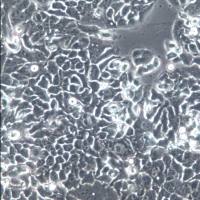

- 英文名:

A-2780

- 细胞形态:

贴壁

- 生长状态: